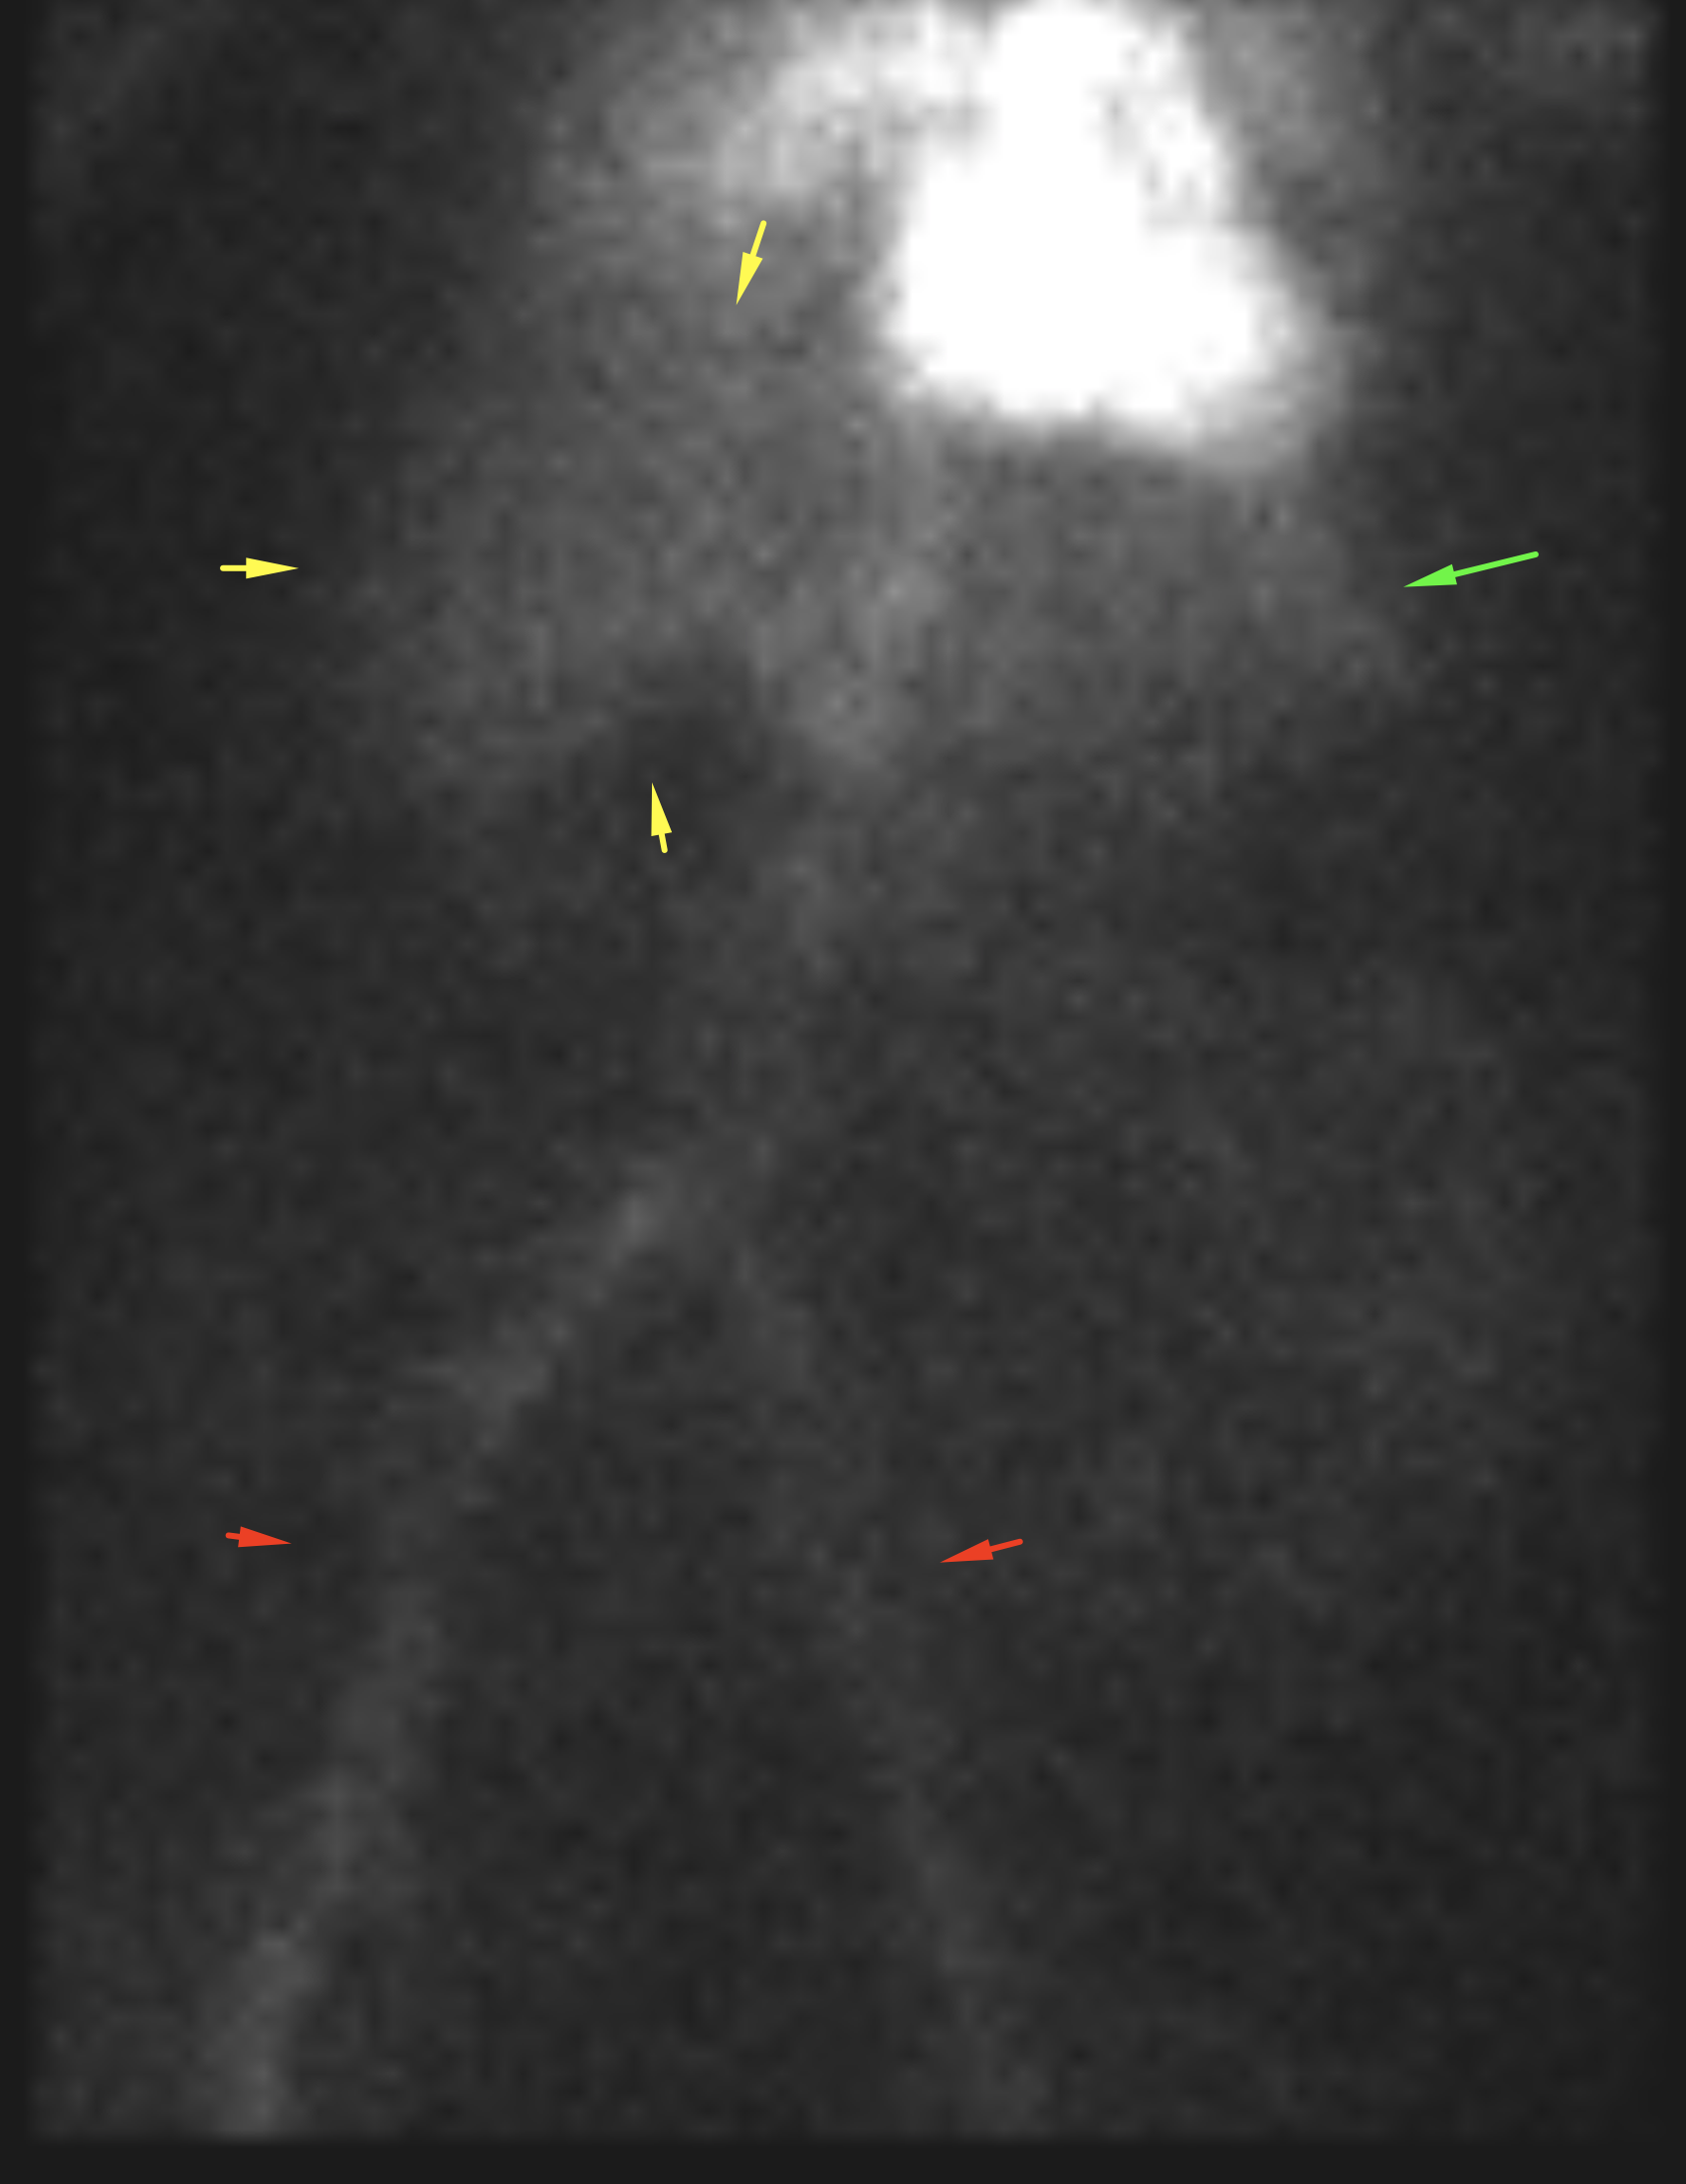

Age: 84

Sex: Female

Indication: Hematochezia with recent negative upper endoscopy and colonoscopy

Radiotracer: Tc99m labeled RBCs

Sample ReportPositive for active GI bleeding, likely originating within small bowel in the left lower quadrant.